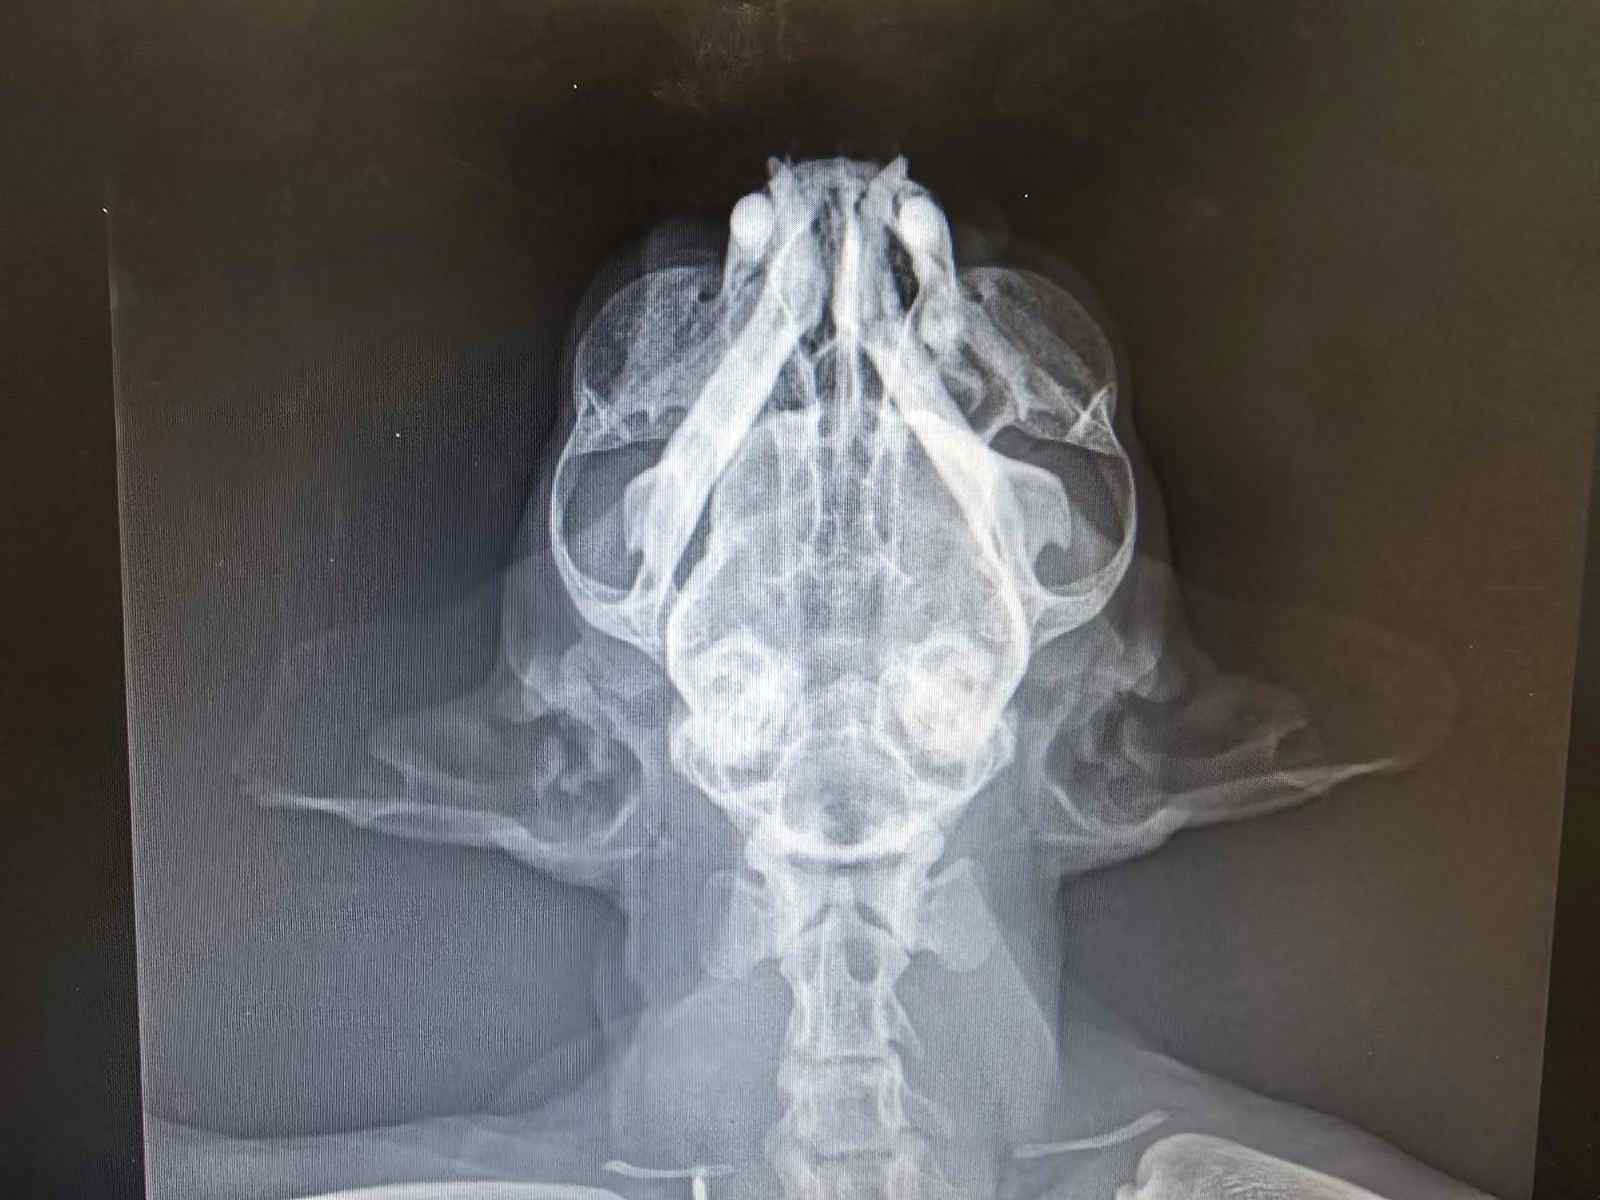

Η πλατεία Αγίας Λαύρας γειτνιάζει με τη λ. Κηφισίας. Το ζώο, που πυροβολήθηκε, ζούσε σε ένα από τα πιο κεντρικά σημεία της πόλης... Οι ακτινογραφίες που έστειλε στο www.zoosos.gr η κα Δημουλά δείχνουν τα δύο σφαιρίδια του αεροβόλου στο σώμα της γάτας...

Έχει επίσης πυροβοληθεί με 2 σκάγια στο θώρακά του και είναι θετικός στο FIP και στο FIV.